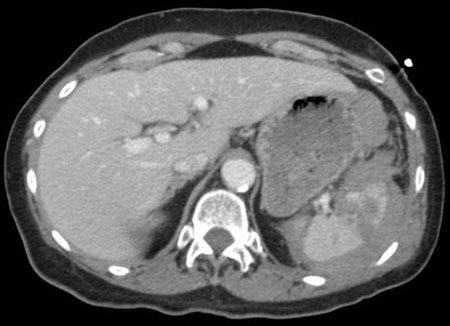

Lesão hepática

história de traumatismo contuso ou penetrante; dor no quadrante superior direito; fraturas de costela inferior direita estão associadas a lesão hepática

sinais de hipovolemia; pode revelar sensibilidade no quadrante superior direito ou plenitude abdominal; o exame físico não é confiável

Primeira investigação

Outras investigações

- avaliação focada com ultrassonografia na avaliação do traumatismo (FAST):

hemorragia intra-abdominal ou intracapsular

Mais - lavagem peritoneal diagnóstica (LPD):

hemorragia intra-abdominal

Mais - arteriografia hepática:

sangramento arterial intra-hepático

- colangiopancreatografia retrógrada endoscópica:

pode identificar complicações tardias de lesões importantes do ducto biliar